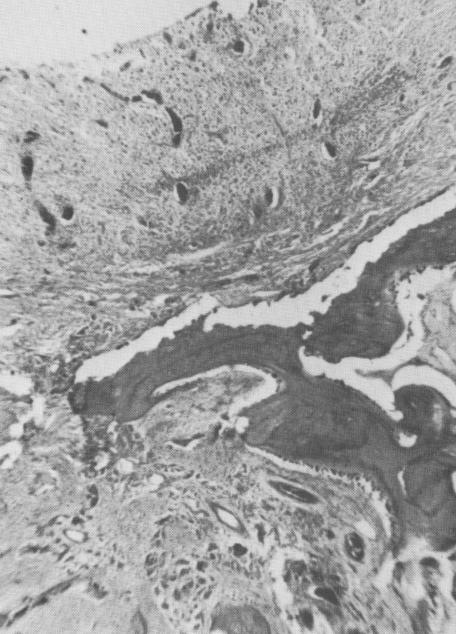

The results when the opening was placed too high coronally are different (Fig. 4-78). The osseous bridge that began to form underwent an inflammatory breakdown analogous to a periodontal abscess. Under higher power magnification, the inflammatory reaction is clearly seen (Fig. 4-79). From these results, one may conclude that osseous bridges grow through openings in the roots of the tooth replica polymer implant. These openings must not be placed too high coronally but should be placed in the lower third of the implant's root if the osseous bridge is to remain healthy.

Fig. 4-79. The inflammation and breakdown are more clearly seen under higher magnification. (Courtesy M. Hodosh.)

1 Inflammation and breakdown of bone tissue at crystalline implant site